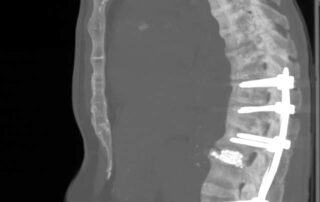

Леонтьєв Олексій2026-01-05T18:54:24+02:00У цьому відео ми демонструємо сучасний малоінвазивний підхід до лікування стенозу поперекового відділу хребтового каналу на рівні L2–L3 у пацієнтки 75 років. Операція виконана методом унілатеральної біпортальної ендоскопії [...]